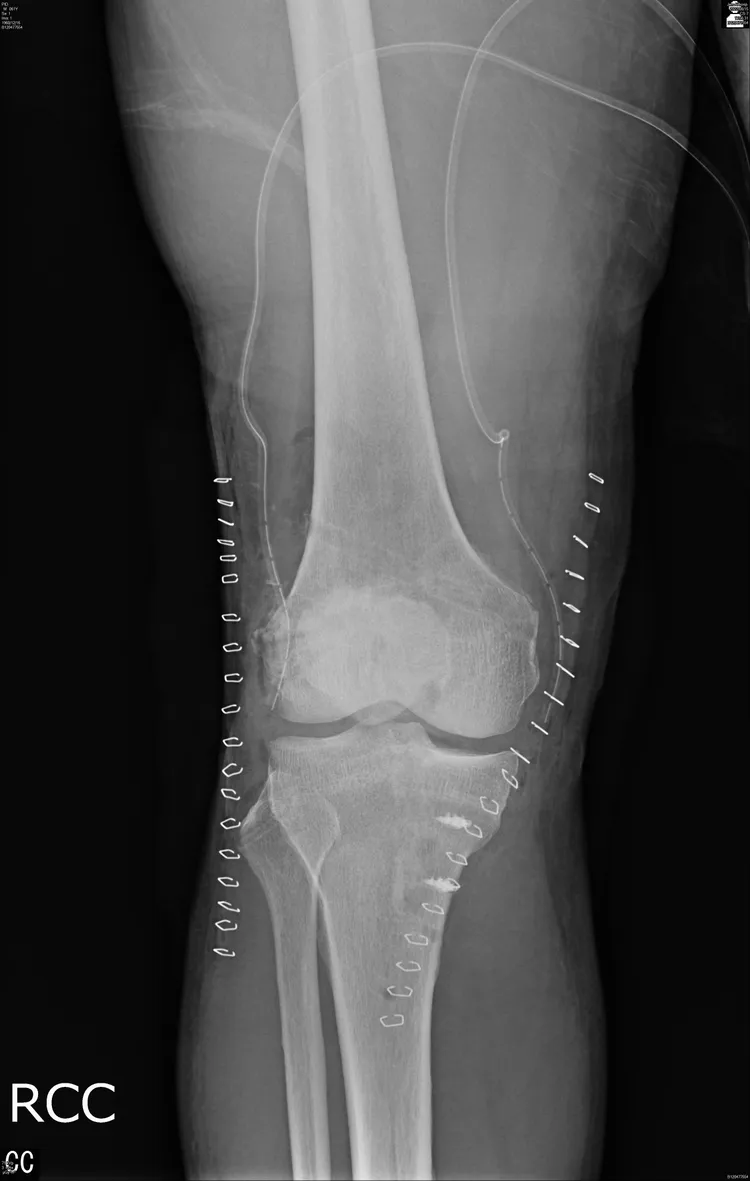

經手術後修復的膝關節。大里仁愛醫院提供